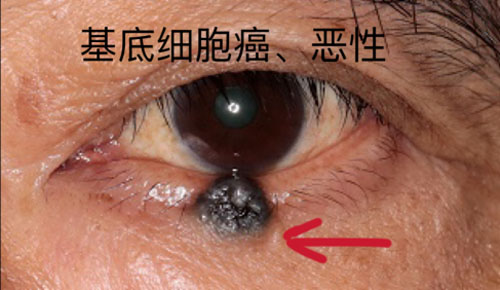

眼腫瘤包括眼瞼、結膜、眼內、淚器、眼眶腫瘤。眼瞼惡性腫瘤常見基底細胞癌,瞼板腺癌、鱗狀細胞癌和黑色素瘤,良性腫瘤常見于色素痣和血管瘤;眼眶腫瘤包括淋巴瘤、腺樣囊性癌、海綿狀血管瘤、神經鞘瘤、神經纖維瘤等;眼內腫瘤以惡性多見,主要見于視網膜母細胞瘤、脈絡膜黑色素瘤、脈絡膜轉移癌等。

對于眼瞼的腫瘤,會充分考慮到顏面部的美容需要,在確保清除病變的同時,完成整形修復。眼瞼腫瘤表現多種多樣,良性病變多生長緩慢,邊界清楚。但是如腫塊突然增長加速,有破潰、出血,疼痛,色素性腫塊有色素播散現象時,您必須引起高度重視。絕大部分惡性腫瘤都發生在中老年人,而年輕人的眼瞼腫塊多是炎癥變化。

如果您到醫院就診,醫生借助放大儀器可以更清楚地觀察病變。部分惡性病變的早期難以完全憑臨床經驗確診,醫生會建議您手術活檢,通過病理來確診。若是惡性,手術切除治療是首選療法,切除的范圍取決于腫塊的大小、位置、深度。皮片移植或皮瓣轉移、游離帶結膜臉板移植、口唇或聘粘膜移植等方法可以修復腫瘤切除后遺留的巨大缺損。眼瞼“寸土寸金”,即使腫塊只相差1毫米,手術也會由簡變繁,所以早治療是重中之重。